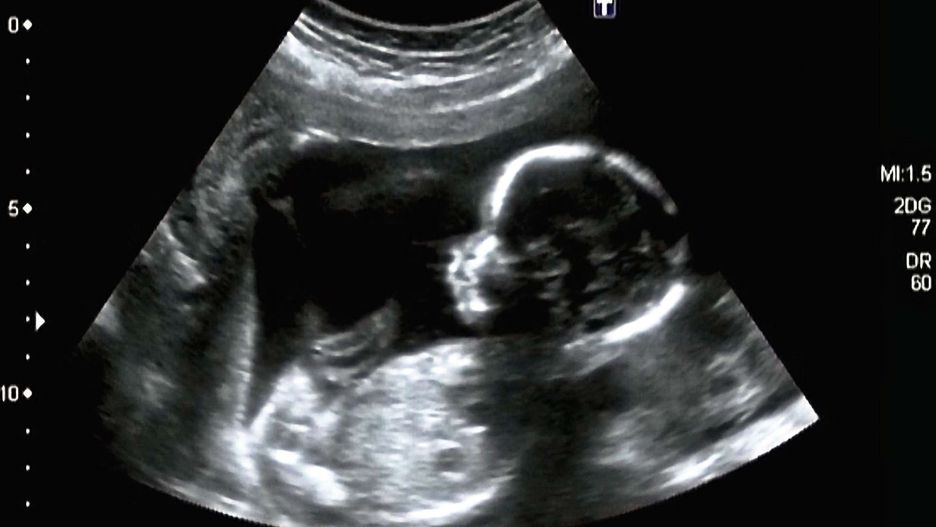

Naukowcy z Uniwersytetu w Durham są zgodni, że dziecko, zanim zawita na świat, wie już, jak płakać. Naukowcom udało się to zaobserwować dzięki zaawansowanej technologii ultradźwiękowej.

Badacze mogli zajrzeć do brzucha ciężarnej kobiety i obserwować rozwój płodu oraz co się z nim dzieje, gdy stymuluje się go hałasm lub wibracjami. Dr Nadja Reissland, główna badaczka i profesor psychologii z Uniwersytetu z Durham uważa, że dzieci ćwiczą mimikę bólu jeszcze przed urodzeniem.

Zespół Reissland mógł przeanalizować rozwój mimiki twarzy dziecka w brzuchu, obserwując za pomocą obrazowania ultrasonograficznego 4D - filmów 3D ruchy płodów w drugim i trzecim trymestrze. Miny dzieci mogą świadczyć o uczeniu się reakcji związanych z płaczem bądź śmiechem.